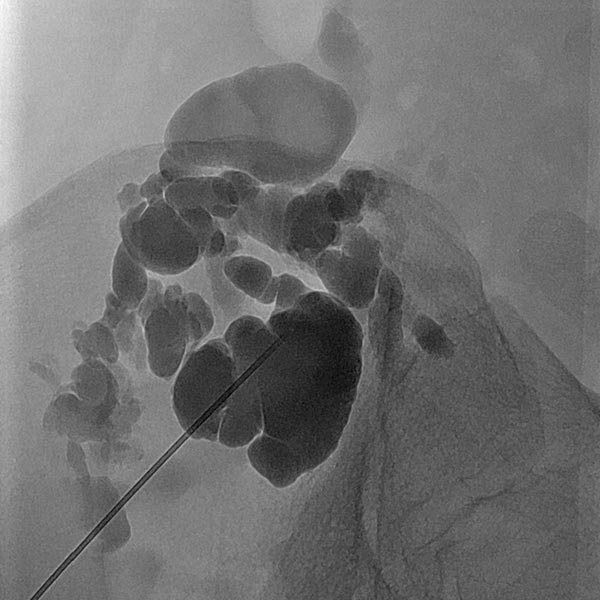

Übersichtröntgenbild im Bereich der rechten Beckenschaufel nach Injektion von Kontrastmittel über die in der LM liegende Nadel. Es kontrastieren sich aus dieser Nadellage weite Anteile der LM, damit optimale Position für die Sklerosierung.

Makrozystische lymphatische Malformationen (LM), die direkt an der Haut liegen, können durch den hohen lokalen Lymphdruck zu einem Durchtritt von Lymphflüssigkeit durch die Haut über kleine Hautbläschen (Lymphvesikel) führen. Diese Areale werden Lymphangioma circumscriptum genannt. Durch eine Sklerosierungstherapie (hier mit Picibanil = OK-432) werden die Lymphkanäle über eine starke lokale Entzündung verschlossen und die Haut abgedichtet. Günstig in diesem Fall die größeren Anteile der lymphatischen Malformation, die miteinander kommunizieren (nach Injektion von KM über die Punktionsnadel sichtbar). Daher sind nur wenige Punktionen notwendig um die gesamte lymphatische Malformation zu sklerosieren. Dieses minimalinvasive Verfahren ist meist auf Dauer schonender als offen operative Maßnahmen, da einzelne, auch kleine Kammern in den oft fuchsbauartig verzweigten LM mit dem flüssigen Sklerosierungsmittel leicht erreicht werden können.